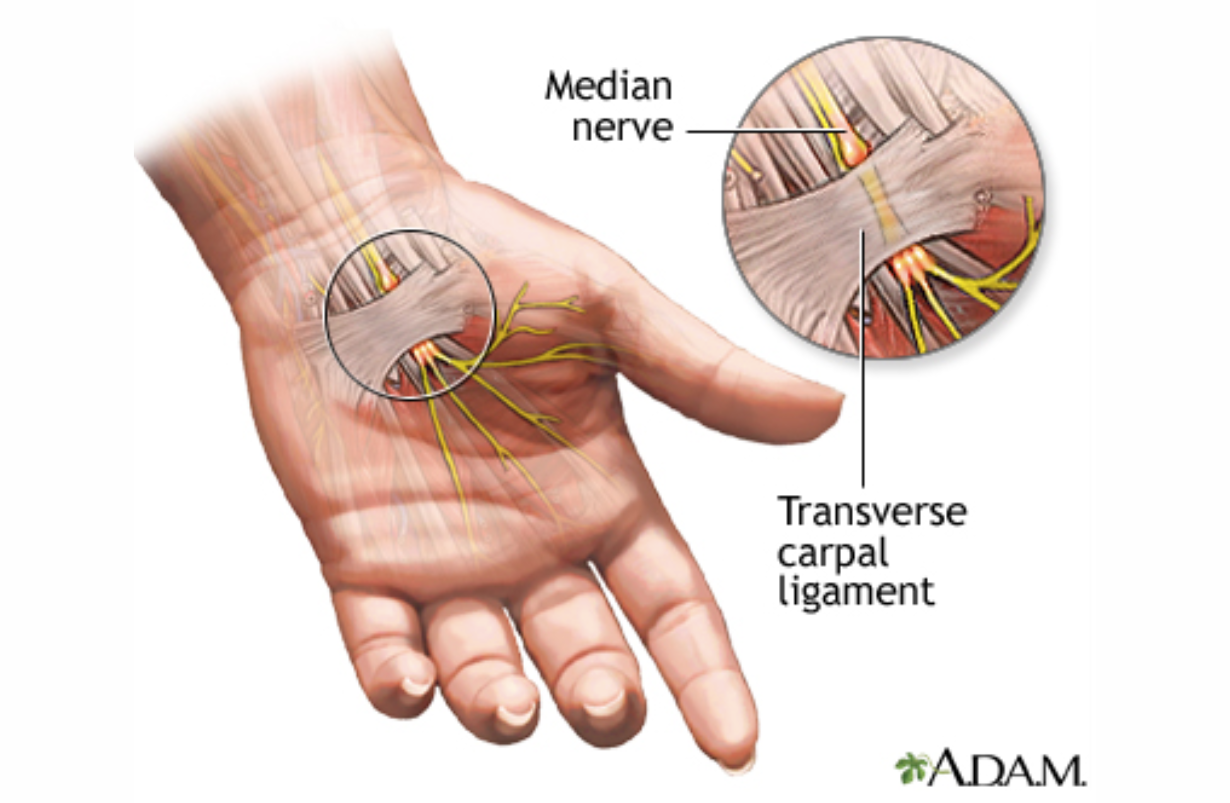

Carpal Tunnel Syndrome

Compression of the median nerve at the wrist. The main effect is weakening of the abductor pollicis brevis, the muscle that gives us humans the opposable thumb. There may also be pain at the wrist and sensory loss along the palmar thumb, index, middle and half of the fourth finger.